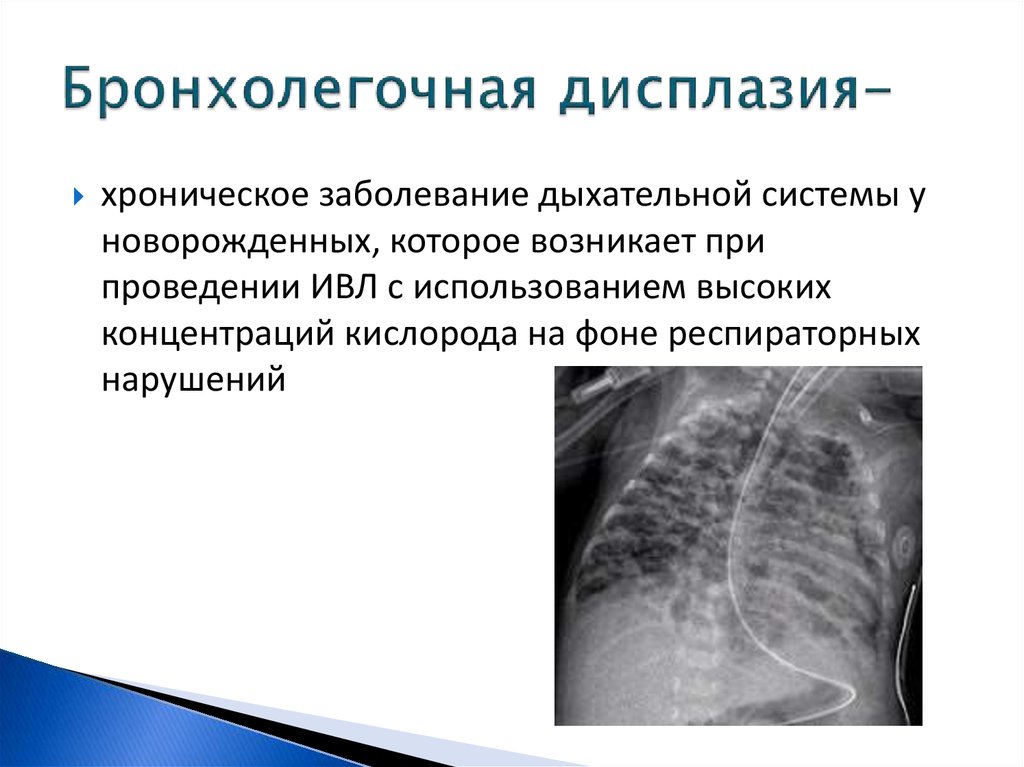

Медицинская тема: легочные осложнения при пневмонии